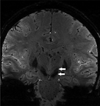

Recent developments in brain imaging methods are on the verge of changing the evaluation of people with Parkinson's disease (PD). This includes an assortment of techniques ranging from diffusion tensor imaging (DTI) to iron-sensitive methods such as T2*, as well as adiabatic methods R1ρ and R2ρ, resting-state functional MRI, and magnetic resonance spectroscopy (MRS). Using a multi-modality approach that ascertains different aspects of the pathophysiology or pathology of PD, it may be possible to better characterize disease phenotypes as well as provide a surrogate of disease and a potential means to track disease progression.